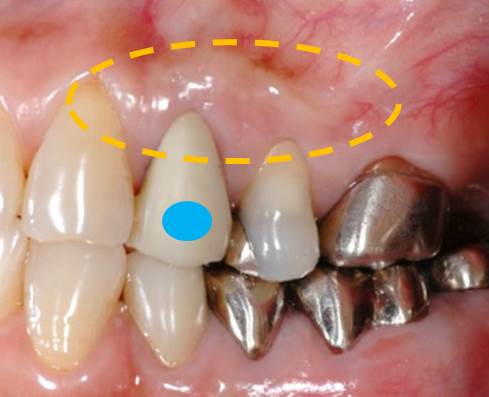

写真の矢印の部分を見ていただくと、歯茎から膿が出てきています。

次の2つのことが考えられます。①歯周病(歯周炎) ②根尖病巣(虫歯が原因で神経を取った歯)のどちらかの疾患が予想されます。今回はどちらでしょうか?

ですから、今回のケースでは、①歯茎からの膿、②歯周ポケットがない、③神経(血管も)を取った歯であるため、歯周病ではなく「根尖病巣」といって歯の中で増えた細菌が原因ということが分ります。